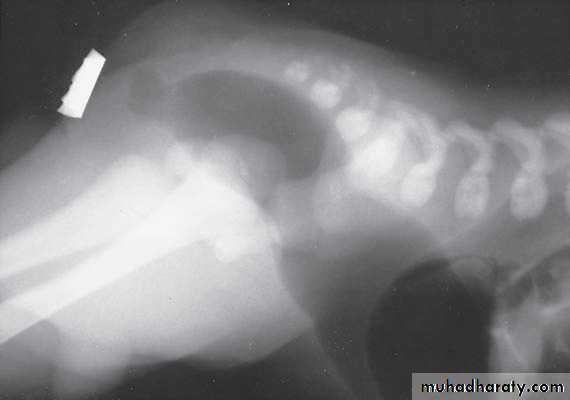

Oesophageal Atresia and Tracheo-Oesophageal Fistula,

First photo:

Diagnosis: pure atresiaDescription: radiolucent abdomen (no gases) + failure of nasogastric tube passage.

Second photo:

Diagnosis: TEF (with fistula)

Description: pass of gases to the abdomen + failure of nasogastric tube passage.

Diagnosis: TEF (atresia with fistula)

Benefits of X-ray:1- to see the failure of nasogastric tube passage.

2- to determine the type of TEF

3- to check the condition of the lung

4- diagnose the associated anomalies (aortic arch – vertebra – ribs)

5- to measure the length of the defect (1-2-3 cm or more)